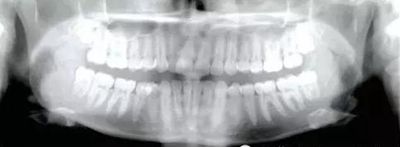

患者為19歲高加索女性,要求矯治中線不齊及上頜右側(cè)側(cè)切牙腭側(cè)異位??趦?nèi)檢查,左側(cè)安氏Ⅰ類尖牙、磨牙關(guān)系,右側(cè)安氏Ⅱ類尖牙、磨牙關(guān)系;上頜中線右偏4mm,下頜中線右偏2mm,16牙根管治療史,16及47有修復(fù)體;覆蓋5mm,覆合4mm,無橫向不調(diào)。功能檢查,顳下頜關(guān)節(jié)無明顯異常,面部及咀嚼肌不對(duì)稱。

治療目標(biāo)為:遠(yuǎn)中移動(dòng)上頜右側(cè)磨牙,達(dá)到安氏Ⅰ類尖牙、磨牙關(guān)系。治療前,拔除上頜左側(cè)第三磨牙,將一直徑2mm,長(zhǎng)14mm的鈦骨釘植入上頜腭中縫,位于切牙孔后4-5mm,中線旁3-4mm。用1.3mm直徑的鉆助攻植入螺紋釘。一周之后,取印模并灌制模型,將螺紋釘?shù)念^部用蠟包圍,從螺紋釘上延伸出連接第一前磨牙的0.8mm的鋼絲??趦?nèi)試戴后,用光固化樹脂將從螺紋釘上延伸出的弓絲與上頜第一前磨牙粘接在一起,0.016*0.022英寸不銹鋼絲片段弓加鎳鈦推簧置于上頜第一磨牙和第一前磨牙間,每側(cè)250g力推動(dòng)上頜磨牙向遠(yuǎn)中,磨牙到位后拍攝頭側(cè)位片。

經(jīng)測(cè)量,上頜第一磨牙遠(yuǎn)中移動(dòng)3.5mm,達(dá)到磨牙Ⅰ類關(guān)系,同時(shí)壓低2mm,而第一前磨牙和上頜切牙沒有明顯的移動(dòng)。上頜第一前磨牙有3°的輕度前傾,這可能是由于上頜只植入了1顆螺紋釘?shù)脑?,作者分析采用兩顆螺紋釘可以減少這種副作用。在上頜磨牙遠(yuǎn)中移動(dòng)過程中,下頜平面角減少了1°,且其持續(xù)到正畸治療結(jié)束。上頜牙弓寬度有輕度擴(kuò)大。